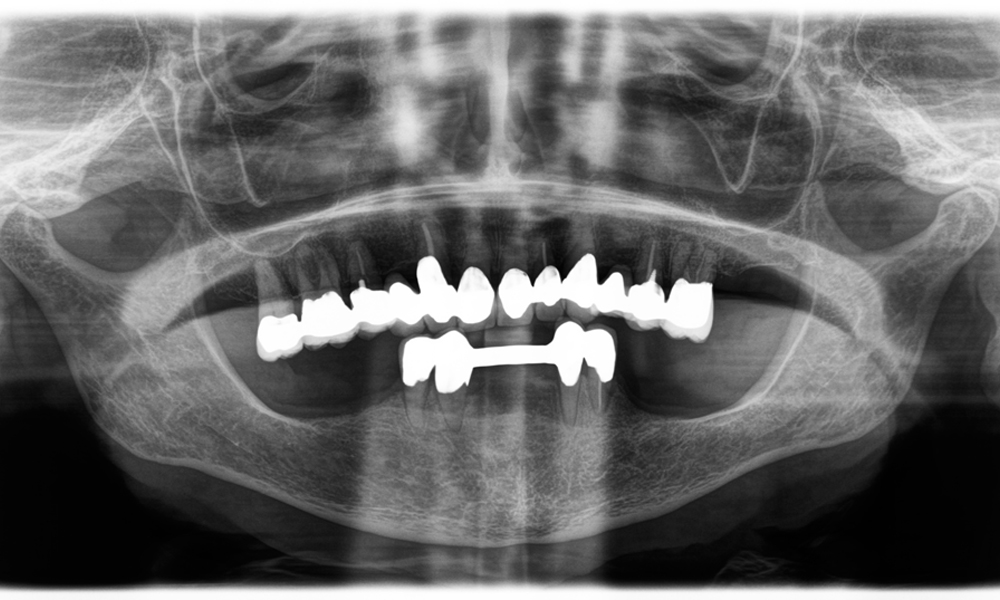

A jaw x-ray from an 81-year-old patient, in front of a black background.

Figure 1: Aesthetic rehabilitation of PFM crowns: Complete removal and replacement of 40-year-old PFM crowns to improve aesthetics in an 81-year-old patient.

The challenge was to remove twelve splinted crowns made of a base metal alloy without damaging the underlying abutment teeth. The handpiece was used to precisely section the ceramic layers and divide the metal framework using a carbide bur, enabling minimally traumatic crown removal. Within just 30 minutes, the old restorations were removed, allowing for the preparation of a new prosthesis, comprising full-contour zirconia in the posterior region and veneered crowns anteriorly. The result was a complete restoration that delivered both functional and aesthetic success (see Fig. 1).